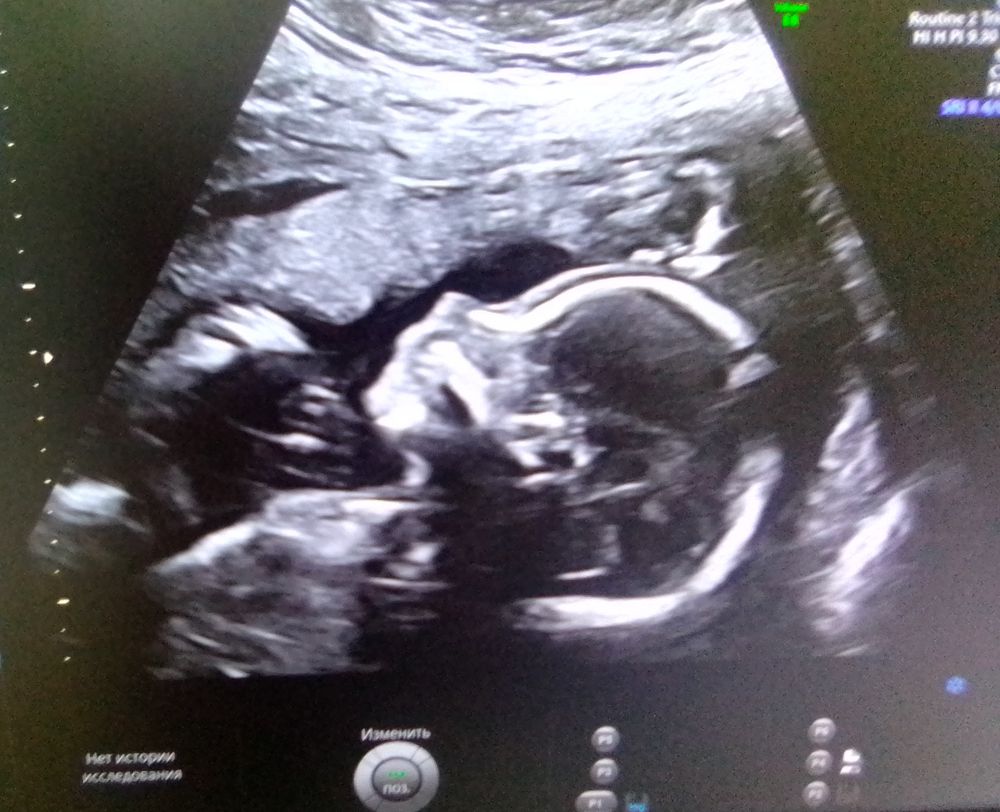

Наше первое фото)))

Изображение По узи 9 недель:)

25.06.2024